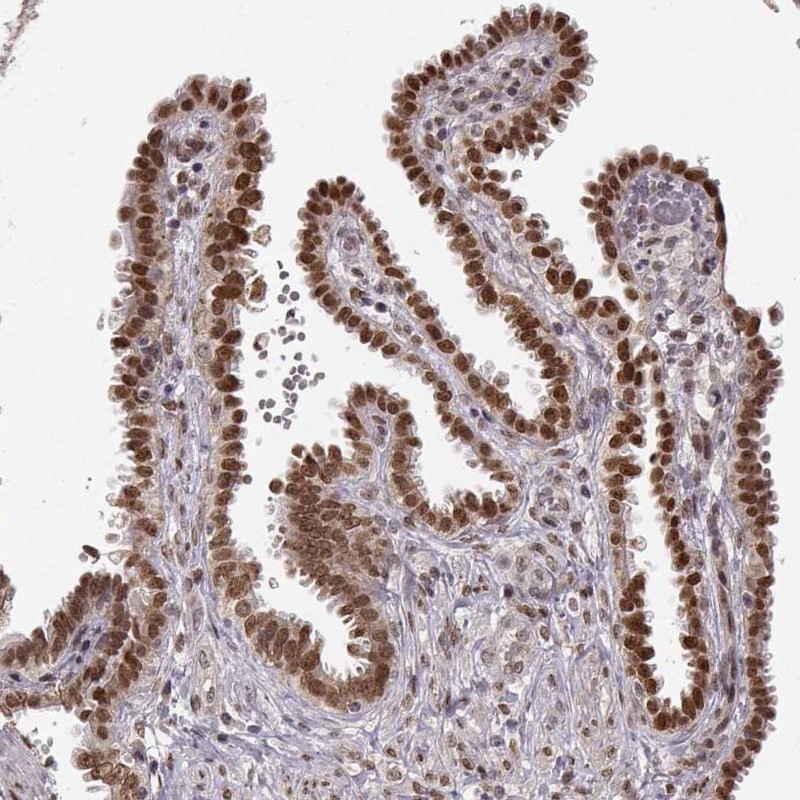

Immunohistochemical staining of human fallopian tube shows moderate nuclear positivity in glandular cells.